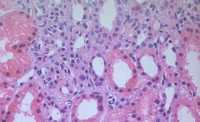

XXXI Congreso Nacional SEAP-IAP

XXXI Congreso Nacional SEAP-IAP